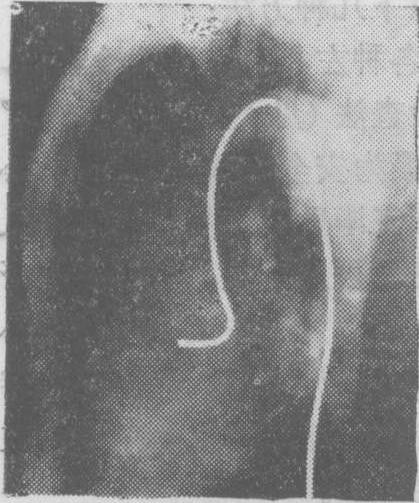

图1 瓣膜型肺动脉口狭窄选择性右心室造影侧位片

图示造影剂从右心室喷入肺动脉时呈细柱状影,肺总动脉呈明显的狭窄后扩张,状如动脉瘤。

(3) 右心室内: 在右心室流出道注射造影剂可显示漏斗部、肺动脉瓣和肺动脉狭窄(图1)。法乐四联症时在右心室注射造影剂可见主动脉及其分支无名动脉、颈动脉、锁骨下动脉和右心室流出道、肺动脉瓣、肺动脉一起显影,可见肺动脉瓣和漏斗部的狭窄情况(图2)。心室间隔缺损有右至左分流时,可见造影剂从右心室进入左心室; 在只有左至右分流的病人,如注射压力高,且造影剂在心室舒张期注入时,则造影剂亦可能通过心室间隔缺损而由右心室扩散入左心室。艾生曼格综合征 (心室间隔缺损型、动脉导管未闭型与主动脉肺动脉间隔缺损型)、大血管错位、右心室双出口、肺动静脉瘘和肺动脉扩张等亦可在选择性右心室造影过程中得到显示。